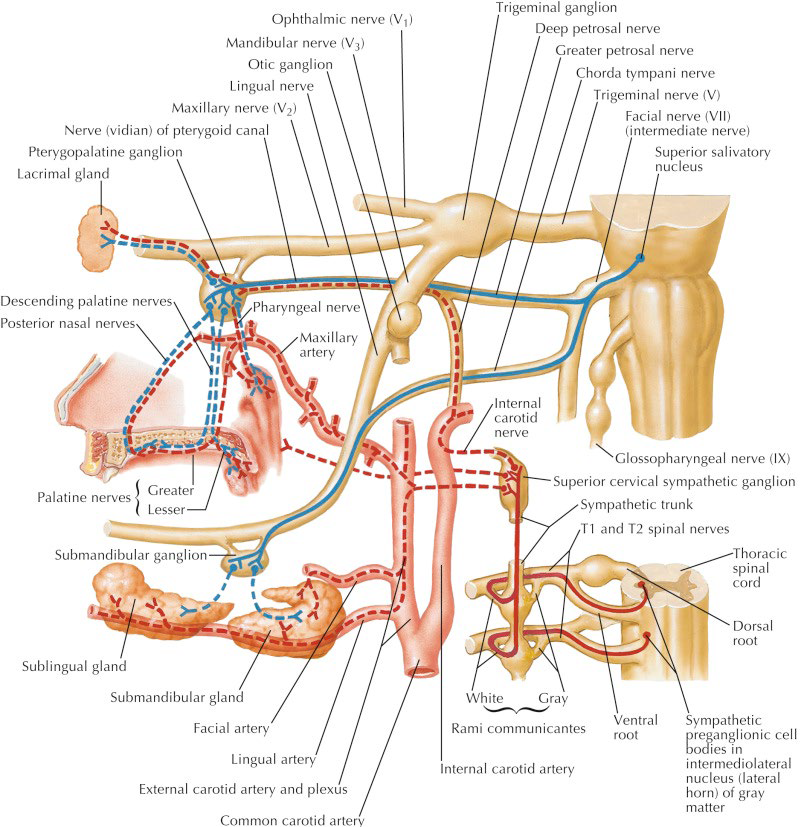

Pterygopalatine ganglion

Greater petrosal n.(Parasymphysis)

- Mucous g.

- Lacrimal g.

Chorda Tympanic n.(Parasymphysis)

- 支配前味覺

- Submandibular, Sublingual g.

Sup. cervical ganglion

支配carotid plexus, pharyngeal plexus